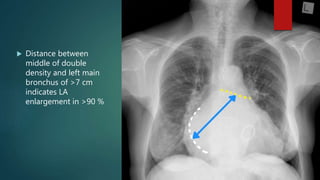

 Distance between

middle of double

density and left main

bronchus of >7 cm

indicates LA

enlargement in >90 %

 Distance between middleof double density and left main bronchus of >7 cm indicates LA enlargement in >90 %